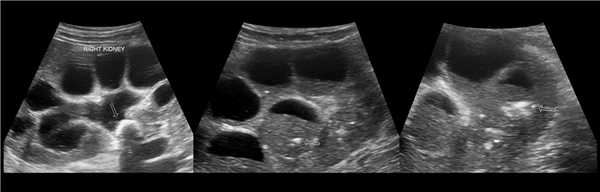

Рисунок. На УЗИ в правой почке расширена лоханка, большие и малые чашечки, мочеточник неизменен. Левая почка и мочевой пузырь без патологических изменений. Заключение: Обструкция лоханочно-мочеточникового соединения справа. Гидронефроз справа, 3 степень.